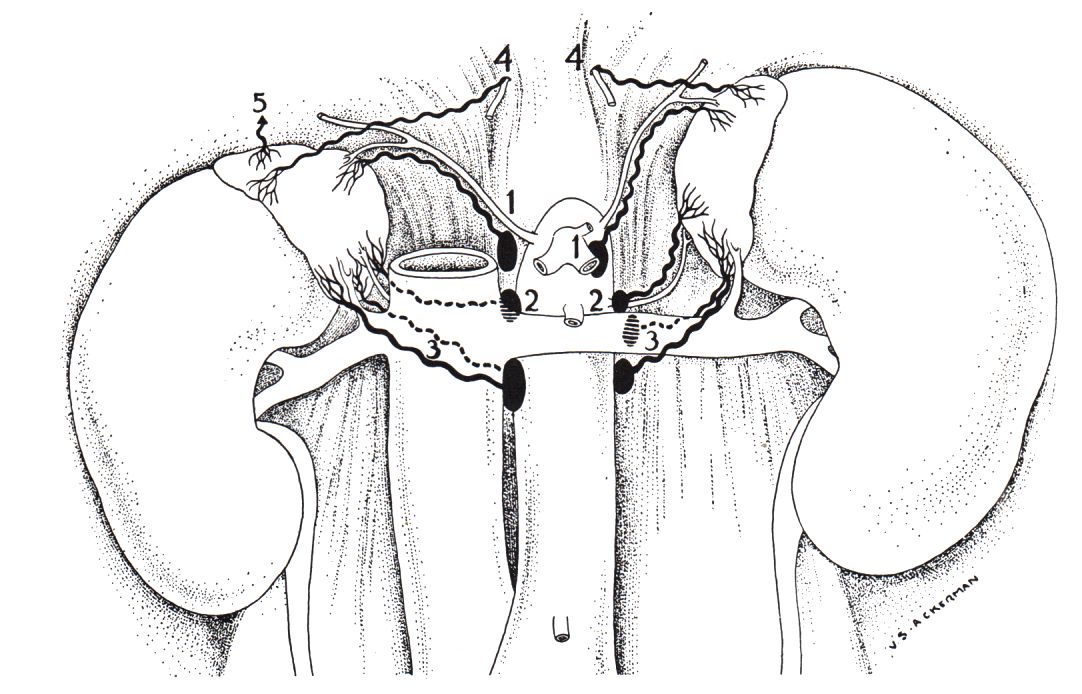

zurück Home Nebennieren - Tumoren Lymphabfluss der Nebennieren

1. entlang der Arteria suprarenalis superior

2. entlang der mittleren Arteria suprarenalis

3. entlang der suprarenalen Venen

4. Lymphgefäße können das Zwerchfell perforieren und dorsale mediastinale Lymphknoten befallen

5. Lymphgefäße direkt zur Leber